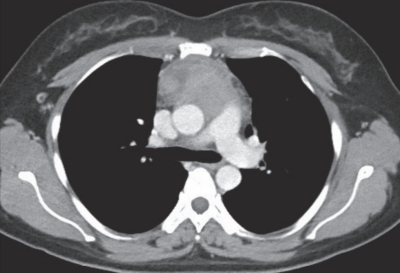

34歳の女性。前胸部痛を主訴に来院した。3か月前から前胸部痛が出現し徐々に増強してきた。体温36.8℃。血圧118/64mmHg。SpO2 98%(room air)。心音と呼吸音に異常を認めない。胸部エックス線写真と胸部造影CTとを別に示す。

考えられる疾患はどれか。2つ選べ。

a. 胸腺腫

b. 神経鞘腫

c. 心膜嚢胞

d. 胸膜中皮腫

e. 悪性リンパ腫